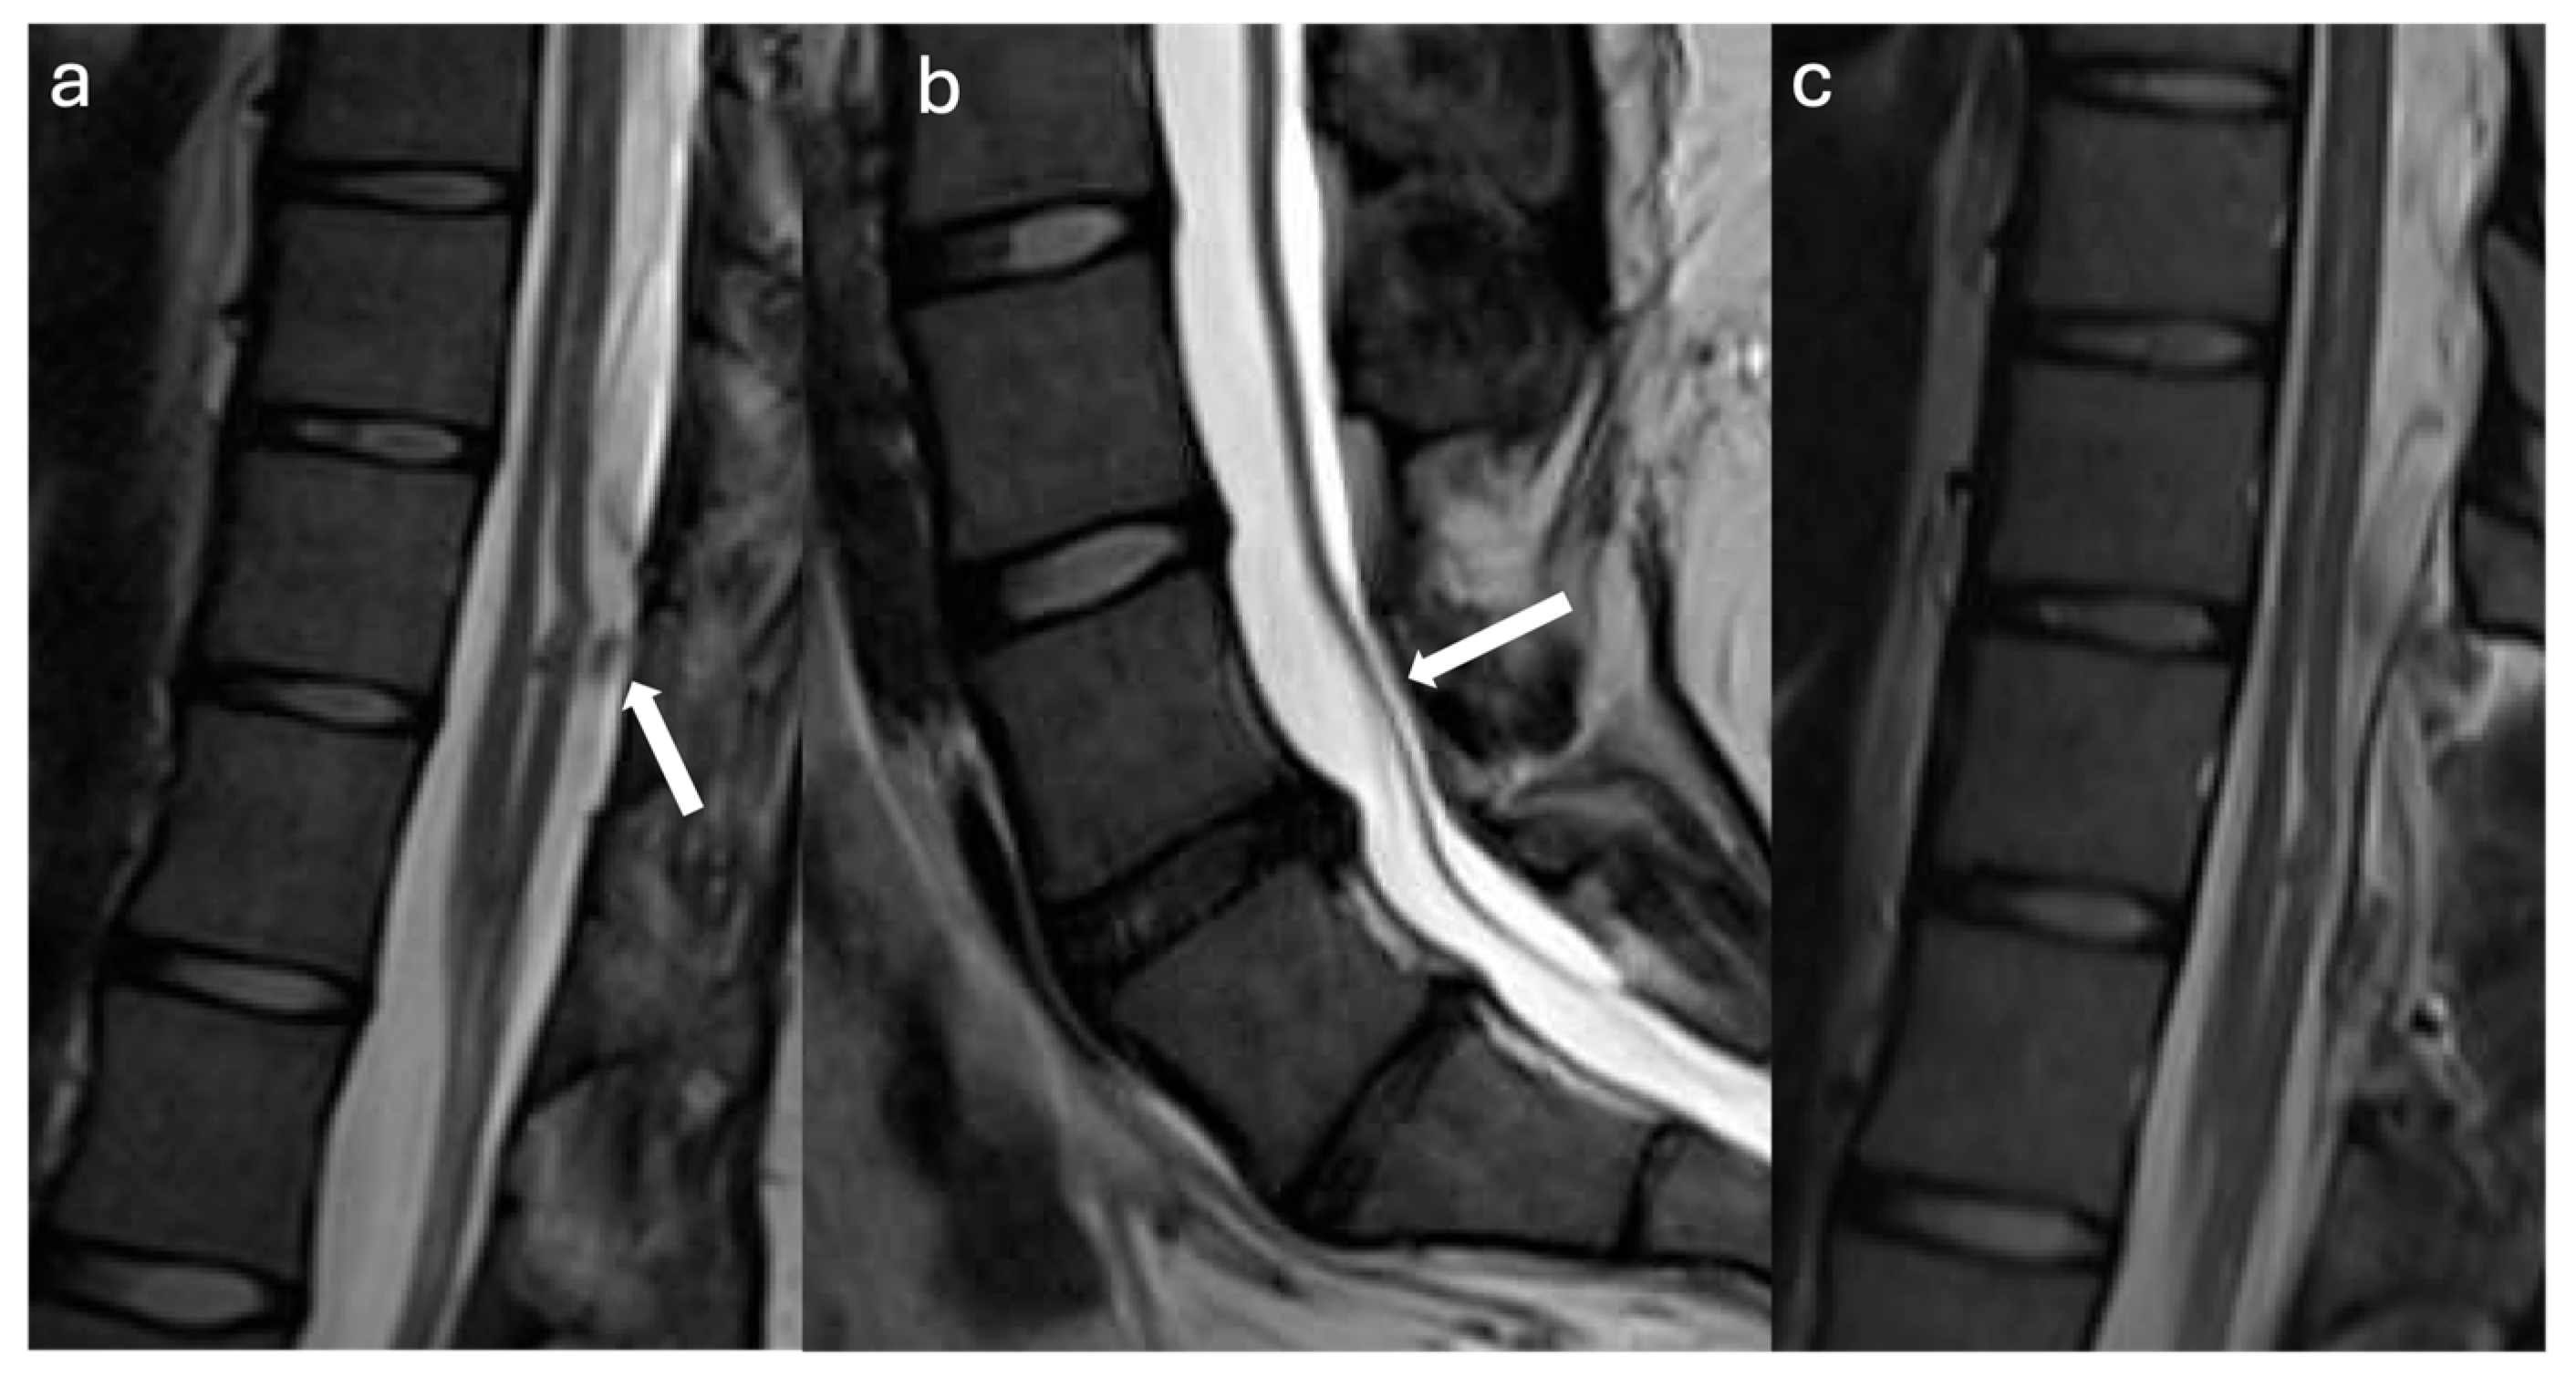

3.2.1. Case #1

3.2.2. Case #2

3.2.3. Case #3

3.2.4. Case #4

3.2.5. Case #5